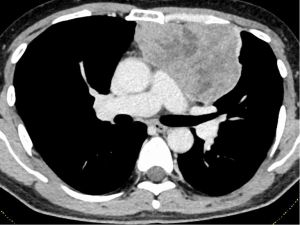

A male in his 60s with an anterior mediastinal mass was referred to Nagoya University Hospital for further examination. He experienced taste disorders including complete loss of sweet, salty, and bitter taste with diminished sour taste just after he was referred to our hospital. He complained as, “I feel that Japanese rice wine (sake) tastes like water.” Chest CT examination revealed an anterior mediastinal mass measuring 5.5 cm in maximal diameter (Figure 2). FDG PET-CT scan showed moderate accumulation in mediastinal mass (SUVmax: 4.45). He showed no symptoms suggesting MG nor elevation in AchR-Ab level (<0.2 nmol/L). Preoperative plasma albumin, serum iron, zinc, vitamin B2, and vitamin B12 levels were within normal limits. He was on no medications before the surgery. He underwent an extended thymectomy via median sternotomy in 2015 (before the COVID-19 pandemic). Pathological examination revealed Masaoka stage II type B1 thymoma. The patient was discharged from the hospital on postoperative day 6. Despite no improvement in taste disorder after surgical thymoma resection, ptosis and double vision appeared 5 years and 2 months after surgery. Moreover, the serum concentration of AchR-Ab was slightly elevated (1.1 nmol/L, normal range, <0.3 nmol/L), and he was diagnosed with MG three months after ptosis and double vision developed; treatment with pyridostigmine (180 mg/body/day) and prednisolone (15 mg/body/day) was initiated. Thereafter, symptoms worsened, resulting in a MG crisis 5 years and 6 months after surgery. There was no change in taste disorder before the MG crisis. After steroid pulse therapy (mPSL, 1,000 mg/day/body), the symptoms have disappeared. Taste disorders gradually recovered within a week. After 6 years and 10 months of surgery, the patient is still alive without MG symptoms (only pyridostigmine, 180 mg/body/day), taste disorder, and thymoma recurrence. All procedures performed in this study were in accordance with the ethical standards of the institutional and/or national research committee(s) and with the Helsinki Declaration (as revised in 2013). Written informed consent was obtained from the patients for publication of this case report and accompanying images. A copy of the written consent is available for review by the editorial office of this journal.